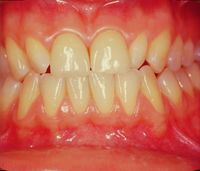

File:Clicker end1.jpg|'''Figure 9a:''' Frontal view of functional neuro-evoked rehabilitation and incisal normocclusal restoration with two crowns in Empress (work performed in 1992)

The finalization of the definitively diagnosed clinical case of DTMs resulted in a restoration of the masticatory function, disappearance of the symptoms as well as an aesthetic improvement. The various phases of the rehabilitation can be followed in the gallery of images in figure 9. In particular, the Functional Neuro-Evoked Centric position is not only centered having moved slightly to the right but also retruded. It is interesting to make a comparison with figure 5a to understand the spatial differences. Element 22, in fact, is no longer in crossbite but in a head-to-head position while element 23 has a much more incisal centric contact with respect to the previous clinical situation, so as to note the occlusal space in the medial area of element 24 which it was generated with the current mandibular spatial position determined with the Functional Neuro Evoked Centric. This new occlusal arrangement was only possible because the stable and mainly frozen centric position in the molar sector. The molars through the previously exposed neuromotor balance on the centric cusp stabilize the occlusion and generate a bilateral balance in the mandibular movements as will be shortly described.